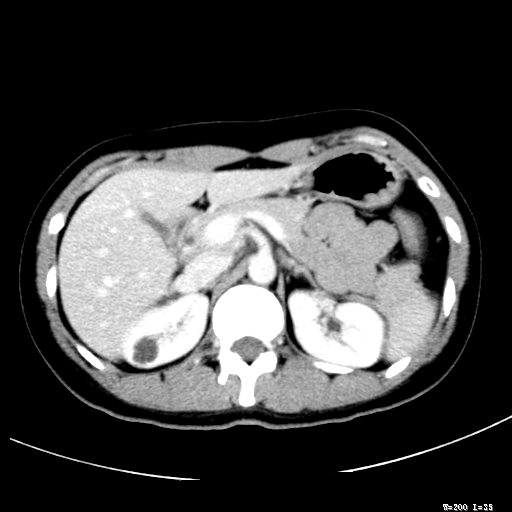

标题: CT25345:右肾占位。

女,30岁,右腰部胀痛3个月。

增强无明显强化,先考虑血管平滑肌脂肪瘤,建议作薄层扫描右mri检查,

增强无明显强化,先考虑血管平滑肌脂肪瘤,建议作薄层扫描右mri检查

支持囊肿或血管平滑肌脂肪瘤。

考虑右肾近上极囊肿;建议必时行mri检查。